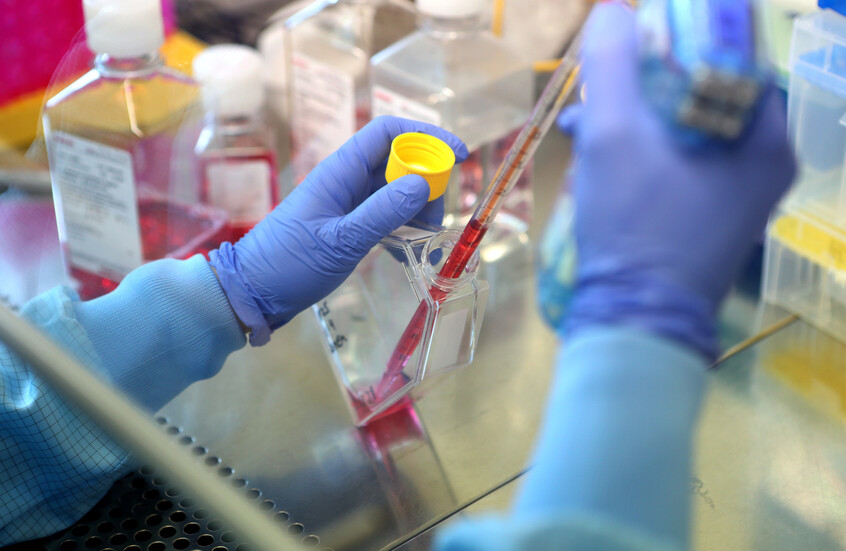

يعتمد لقاح لانغفاكس على أن خلايا سرطان الرئة تظهر على سطحها بروتينات شاذة تعمل كإشارات خطر، تنتج عن طفرات مسببة للسرطان في الحمض النووي. تُعرف هذه البروتينات باسم “مستضدات نيو” (neoantigens) و”مستضدات مرتبطة بالورم”، وتظهر في مرحلة مبكرة جدا من تكوين الورم.

يحمل اللقاح سلسلة من التعليمات الجينية التي تدرب الجهاز المناعي على التعرف على هذه المستضدات وتدمير الخلايا الشاذة قبل أن تتحول إلى سرطان خبيث، باستخدام التقنية نفسها التي طورتها جامعة أوكسفورد خلال جائحة كوفيد-19.